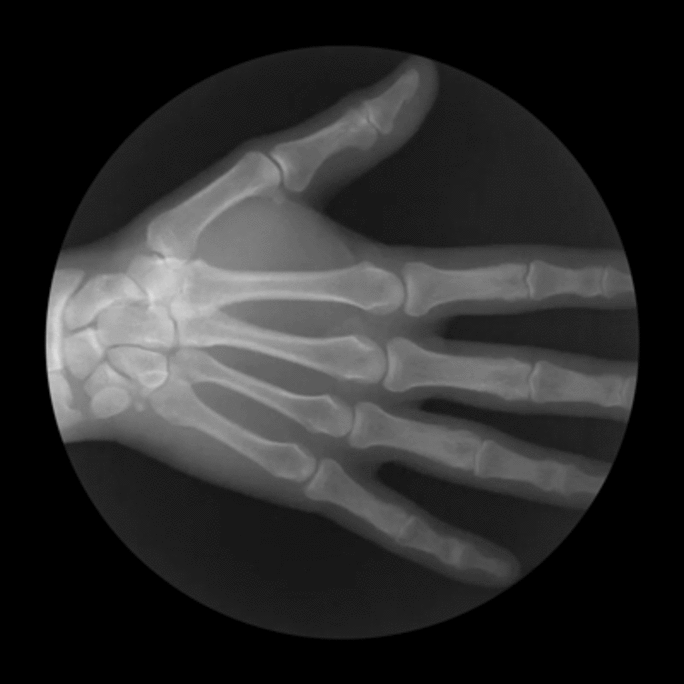

Après, comme la radio était libre aussi, bon j'en ai bavé pas mal aussi, parce que devant toujours me propulser ici du brancard sur la table - mais là sans l'attelle et bien " entendu " en petite culotte - mais là y avait une nana qui contrôlait les faits & gestes de son acolyte mâle de manipulateur (en radiologie), alors qu'avant, la grosse toubibe était bien au-dessus de tout ça et ne pensait qu'à m'enfoncer et mon genou si possible de la façon la plus " élégante " je veux dire, d'après ses propres critères disons, la plus fine possible : étant au-dessus de ça, elle s'est con-tentée de ne pas prendre les choses en main, ce qui a quelque peu arrangé mes affaires ⇒ au moins, mon genou ne serait pas luxé 3 fois → en radio, le mec non plus n'a pas pu toucher, au moins avec ses mains non plus, surveillé lui par sa collègue, et donc là aussi je me suis dépatouillée pour soulever toujours moi-même tout le bazar pour le mettre sur la plaque, qui m'a bien rafraîchie l'articulation assez sous pression - comme  y avait pas de fracture, les deux se sont cons-tentés de m'informer savamment que j'avais une entorse et hop ! j'ai fait le chemin inverse, me re-glissant de la table sur le brancard toujours avec un petit intervalle d'une quinzaine de cms pour pimenter-agrémenter la chose, et roulez jeunesse ! on m'a re-brinquebalée dans le box toujours libre et propre pour la future inspection cadresque, pour que je soie également informée du verdict doctoral de ma con-sœur, qui m'a arraché le cliché mais des mains, donc pour me dire aussi que j'avais bien une entorse puisque c'était pas cassé, et qu'il y avait beaucoup de sang

Illustration 4